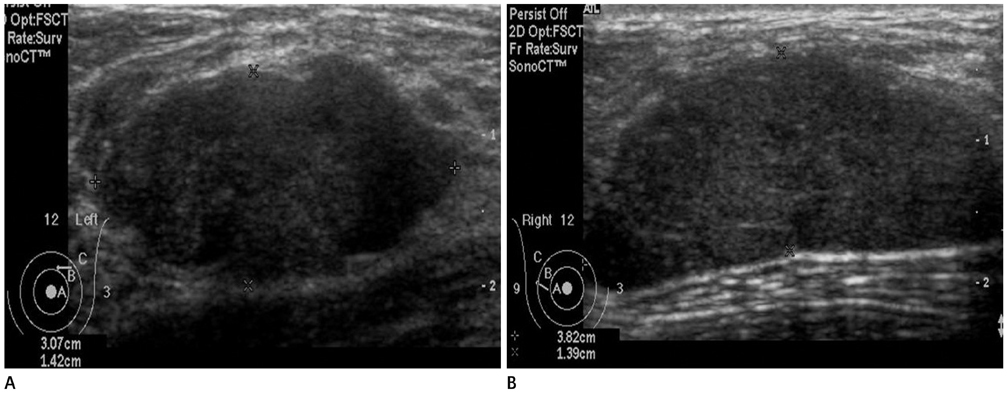

- The purpose of this study is to review various breast diseases in children and adolescents and to illustrate the sonographic findings. We reviewed the cases at our institution in order to identify breast disease in children and adolescent patients who underwent sonography and mammography. Breast disease in children and adolescents included developmental disturbance, infection, benign tumors and inherent defects. In contrast to adults, the radiologic findings of malignant breast conditions in pediatric populations have rarely been reported; however, we show ductal carcinoma in situ with juvenile fibroadenoma and rhabdomyosarcoma. During childhood and adolescence, the recognition and correct identification of physiologic breast development and specific lesions in breast entities on radiologic findings is most helpful in identifying and characterizing abnormalities and in guiding further investigation.